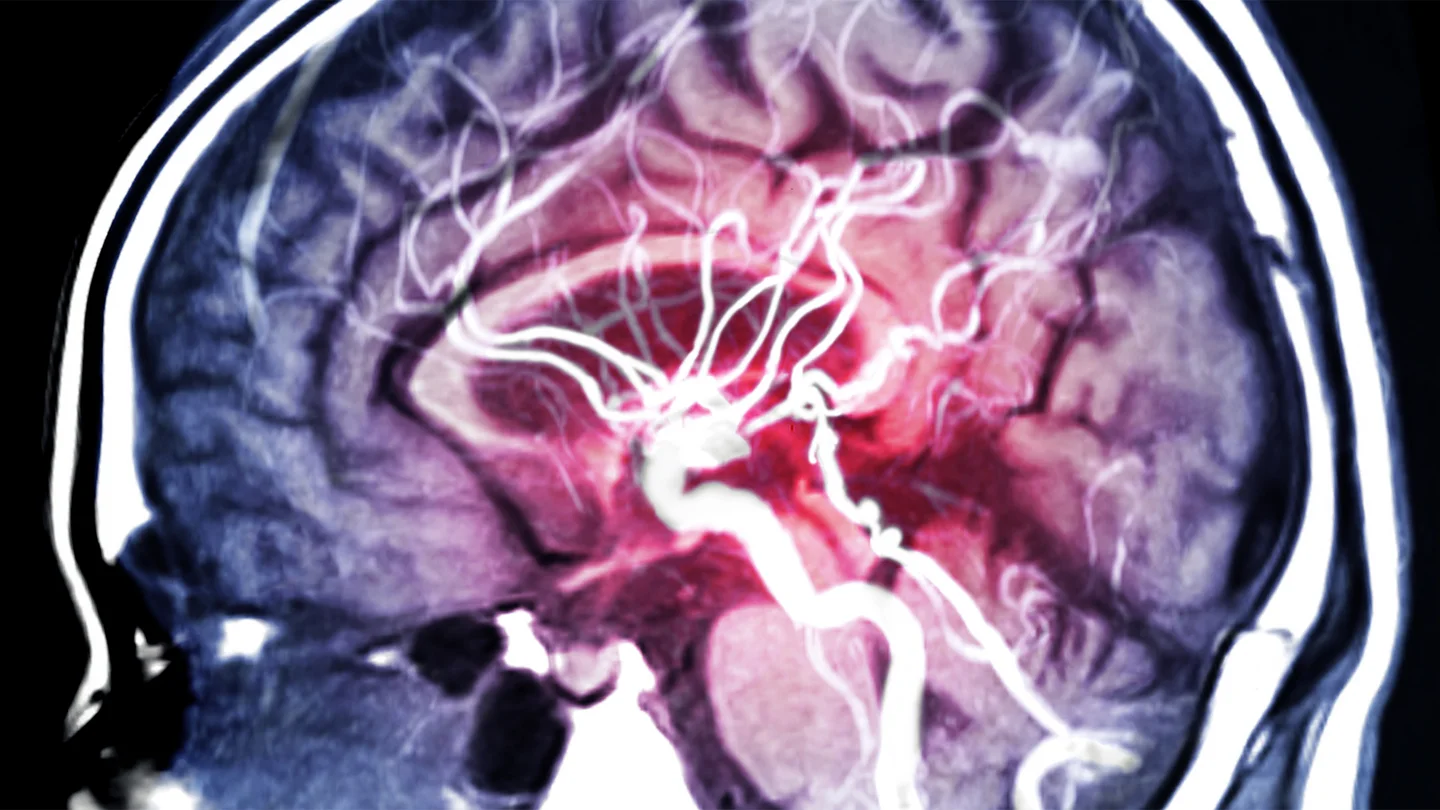

A brain aneurysm is a bulge in an artery in the brain. Many people who have an aneurysm can go their whole lives without noticing it. In some cases, brain aneurysms are discovered by chance. Certain factors increase the risk of a brain aneurysm rupturing and causing a life-threatening brain hemorrhage.

Menschliches Gehirn im Querschnitt: Blutgefäße und Hirnschlagader sind sichtbar. Menschliches Gehirn im Querschnitt: Blutgefäße und Hirnschlagader sind sichtbar.

What is a brain aneurysm?

An aneurysm is a pouch-shaped or berry-shaped bulge in an artery. It occurs when part of the wall of a blood vessel is no longer strong and elastic and bulges outwards as a result.

Aneurysms can occur on various arteries, for instance the abdominal aorta. If one of these bulges occurs in an artery in the brain, this is referred to as a brain aneurysm or cerebral aneurysm. This type of aneurysm often develops at branches in the arteries that supply blood to the brain. If a brain aneurysm ruptures, it may cause a life-threatening brain hemorrhage.